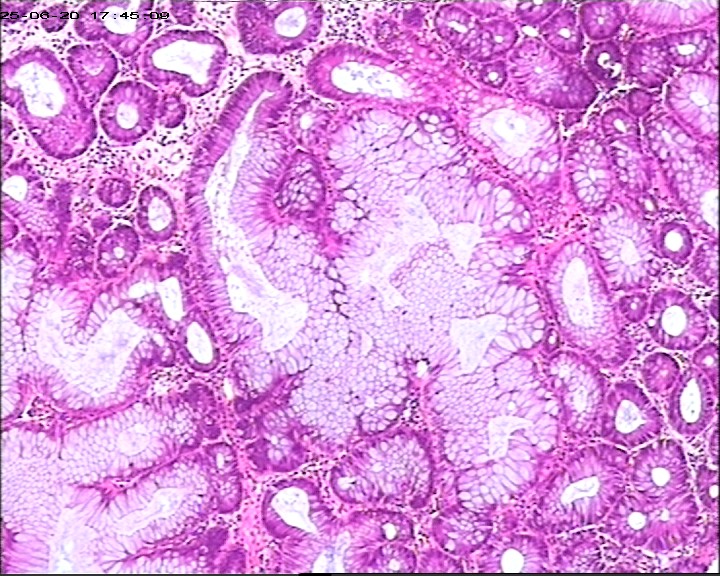

直肠息肉组织,请帮忙看看,谢谢

性别

男

年龄

66岁

临床诊断

一般病史

腹痛1周加重伴黑便3天

标本名称

直肠息肉

大体所见

灰白组织1块,直径0.6cm。

图1

增生性息肉